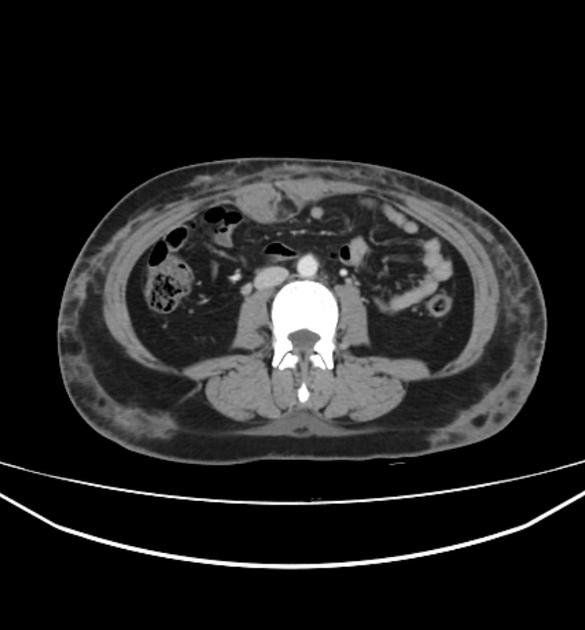

5.2. CT Scanner

CT Scan được sử dụng để phân biệt chính xác giữa viêm mô tế bào nông và viêm mô tế bào sâu.

Trong bệnh viêm mô tế bào không biến chứng, CT cho thấy da dày lên, có các vách trong lớp mỡ dưới da và cân mạc nông bên dưới dày lên. Nếu nhiễm trùng lan đến các mô sâu hơn, áp xe mô mềm, viêm cơ nhiễm trùng, viêm cân hoại tử và viêm tủy xương đều có thể được phát hiện bằng CT.